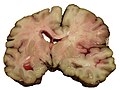

Sampling - sections (autopsy)

Standard histologic sections:

| Site | Routine[8] | Head injury[9] | Epilepsy[10] | Dementia[11] |

|---|---|---|---|---|

| Frontal cortex | Y [1] | Y - bilateral parasagittal [2] | N | Y - middle frontal gyrus [1] |

| Cingulate gyrus | N | N | Y - parasagittal [1] | Y [1] |

| Basal ganglia & internal capsule |

Y [1] | Y - bilateral with corpus callosum [2] | Y - caudate, putamen, globus palidus [1] |

Y - putamen, globus palidus [1] |

| Basal ganglia, internal capsule, thalamus |

N | Y [2] | N | N |

| Temporal lobe | N | N | Y - superior & middle temporal gyri [2] | Y - superior & middle temporal gyri [1] |

| Hippocampus | Y [1] | Y - bilateral [2] | Y - also parahippocampal gyri [2] | Y - also parahippocampal gyri [1] |

| Splenium of corpus callosum | N | Y [1] | N | N |

| Parietal lobe | N | Y - centrum semiovale (unilateral) [1] | N | Y - inferior [1] |

| Occipital cortex | Y [1] | N | N | Y [1] |

| Midbrain | Y [1] | Y [1] | N | Y [1] |

| Cerebellum (with dentate gyrus) |

Y [1] | Y - bilateral [2] | Y - also vermis [2] | Y [1] |

| Pons | N | Y [1] | N | Y [1] |

| Medulla | Y [1] | Y [1] | N | Y [1] |

| Total sections | [7] | [15] | [8] | [11] |

An absolute minimum:[12]

- Hippocampus.

- Cerebral cortex.

- Brainstem (midbrain).

- Cerebellum.